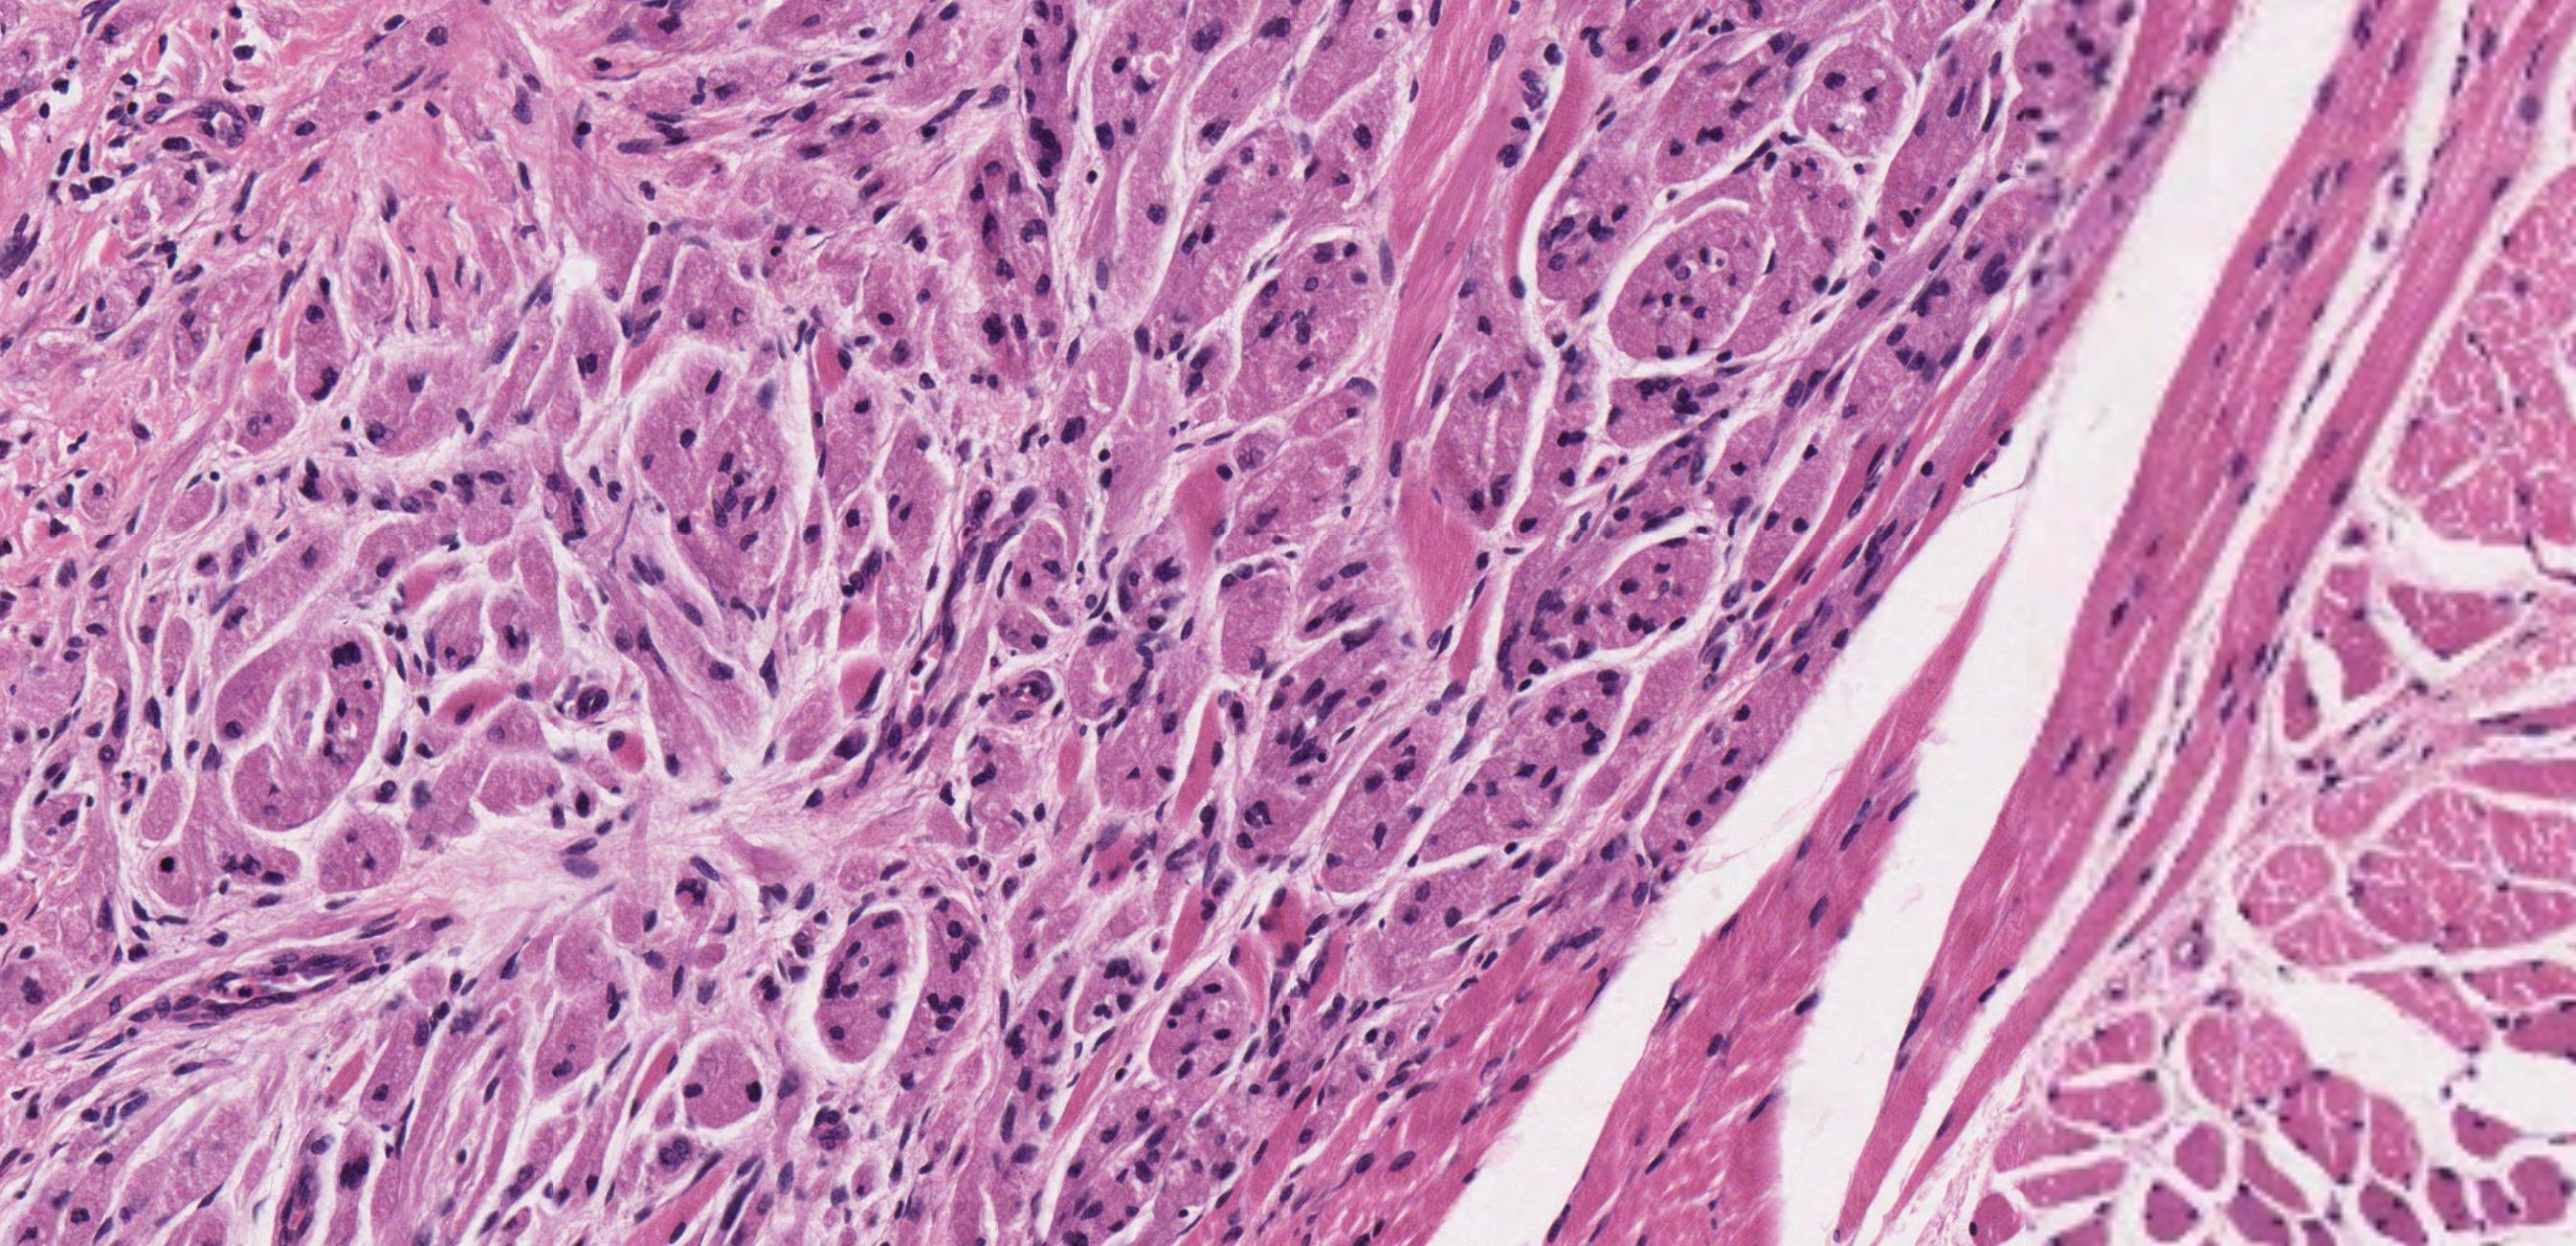

• Nodular mucosa with circumscribed tumour with infiltrative periphery • Large cells with eosinophilic granular cytoplasm • Is surface epithelium normal?

Case 4- Salient points

??

Case 4 Diagnosis

Granular cell tumour